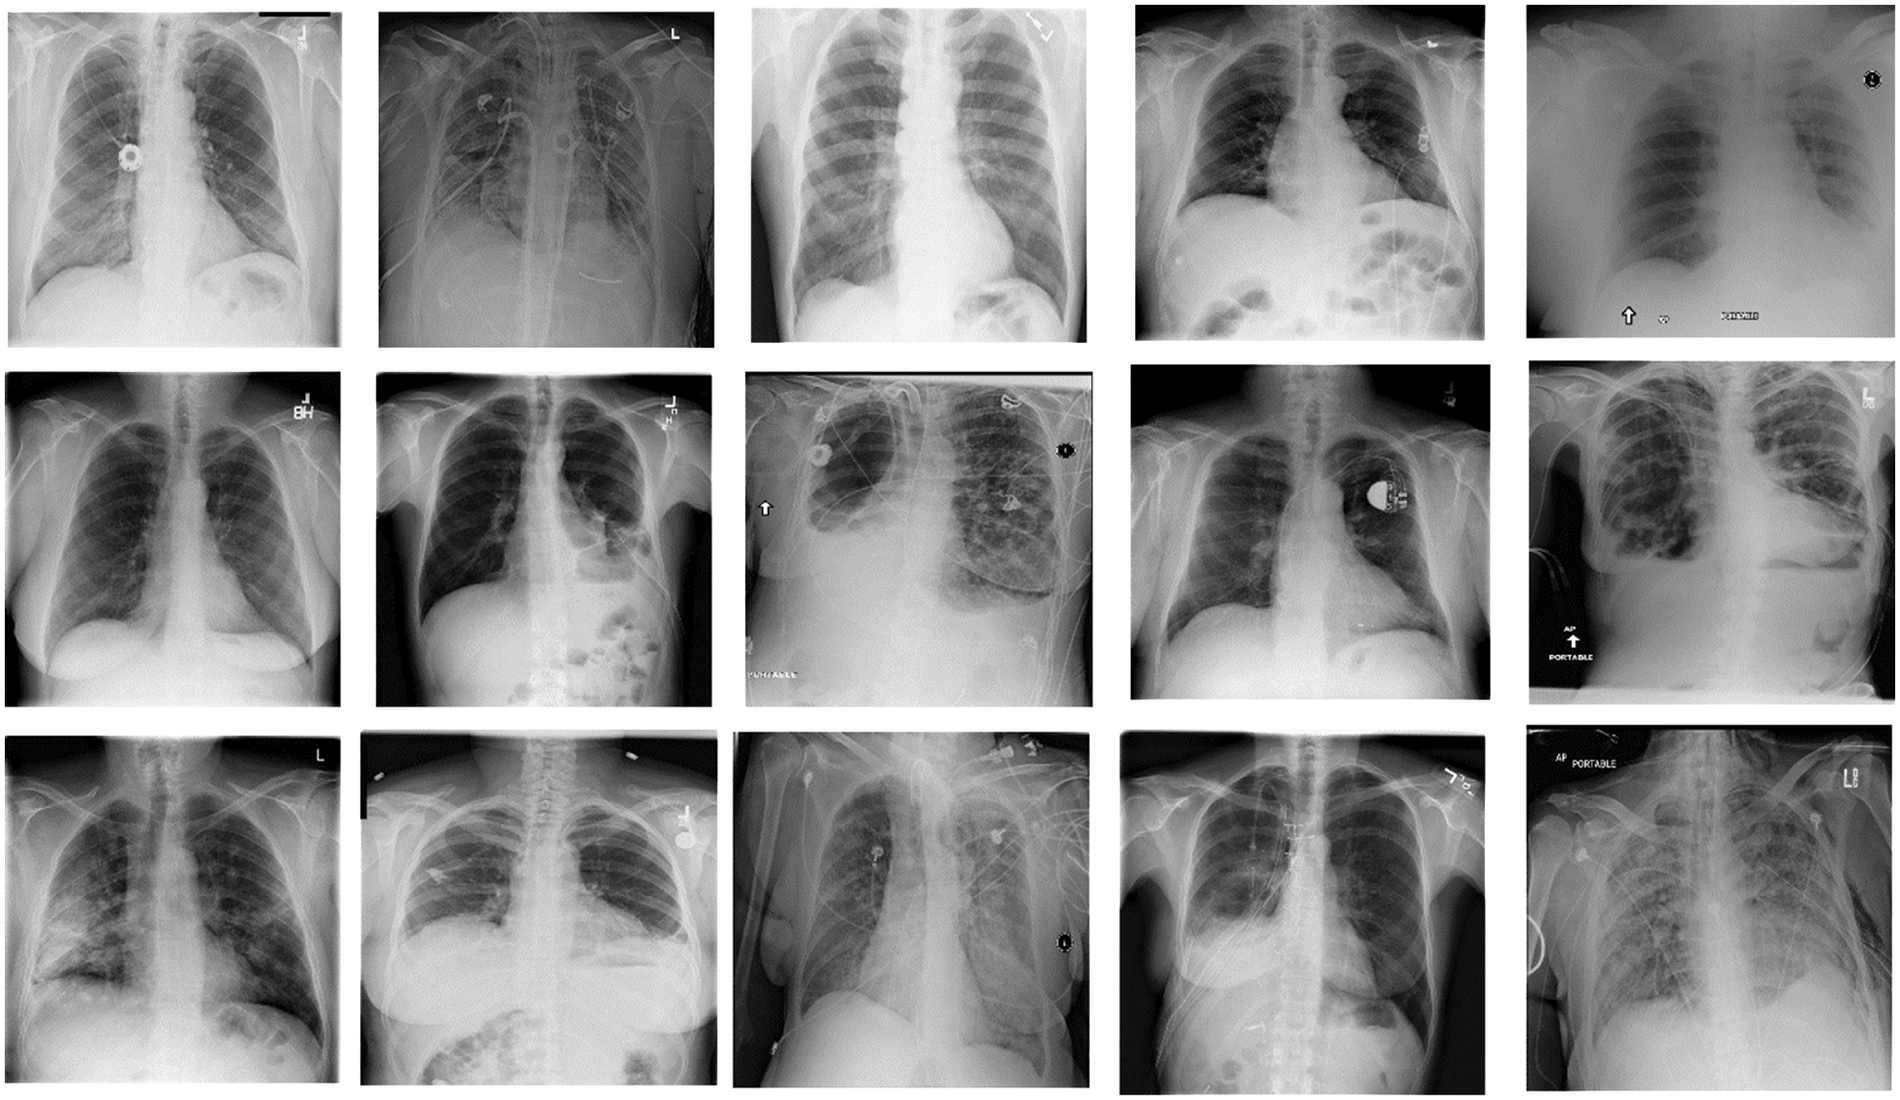

This research uses the pneumothorax medical image dataset from the Kaggle repository. The small pneumothorax dataset consists of 2027 medical images of lungs collected by the radiologist during the chest X-ray of patients. Pneumothorax small dataset (2027 images) used for binary classification task either Pneumothorax or not. The total training data is 2027. Fig. 2 represents the samples of the Pneumothorax dataset in the form of chest X-ray images. The dataset is divided into two dormers because this study works with two clients, each with its data. The dataset was split into training and testing data, with 75% data for training models and 25% for testing the models.

Figure 2: Samples of pneumothorax dataset (chest X-ray images)